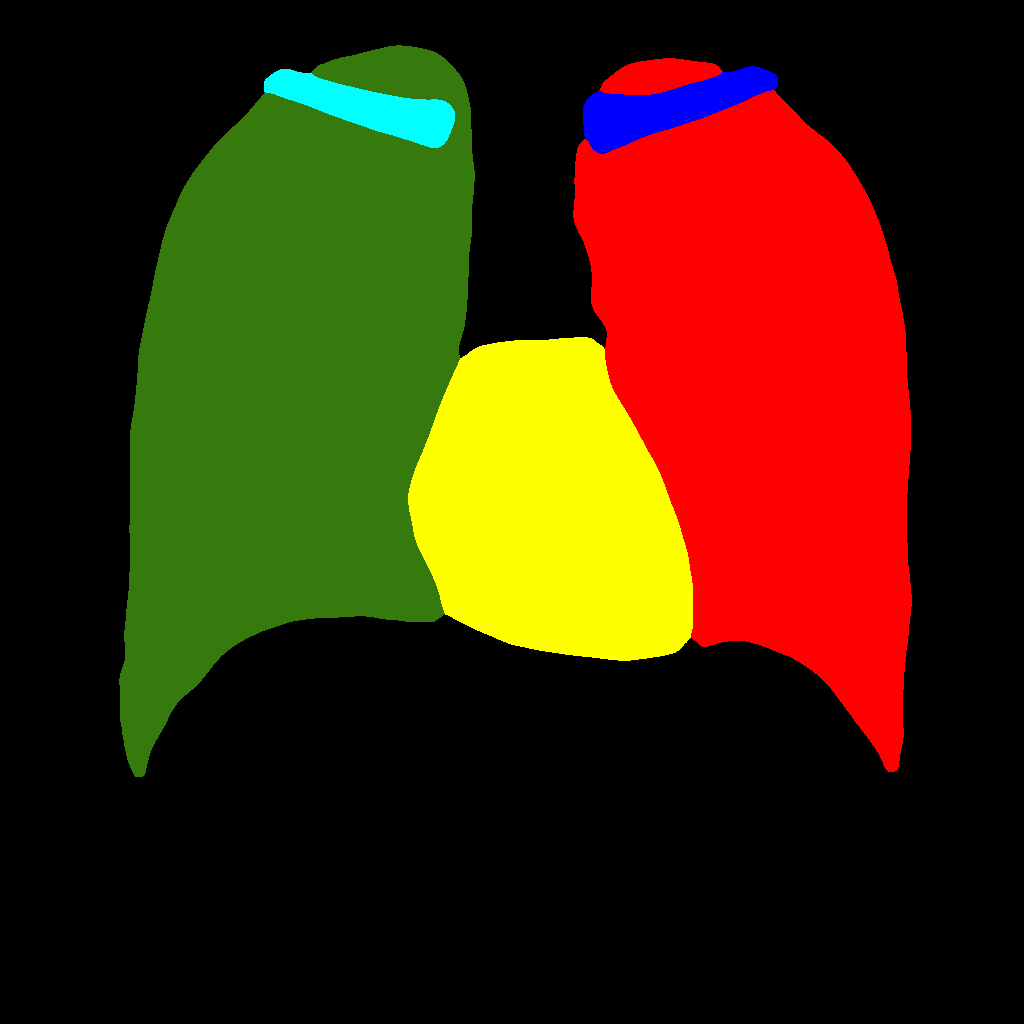

This baseline approach consists in stacking X–ray images and labels into two different channels, which are simultaneously fed into the PGGAN. Therefore, the PGGAN is trained to generate pairs composed by an X–ray image and its corresponding label (see Figure 1).

Figure 5 and Figure 6 display some examples — randomly chosen from all the generated images — of the label–maps and the corresponding chest X–ray images generated with the three methods described in Section 3, using the FULL_DATASET and the TINY_DATASET, respectively. We can observe that, with the single and two–stage methods, the images tend to be more similar to those belonging to the training set. For example, in most of the generated images there are white rectangles, which resemble those present in the training images, used to cover the names of both the patient and the hospital. Instead, the three–stage method does not produce such artifacts, suggesting that it is less prone to overfitting.